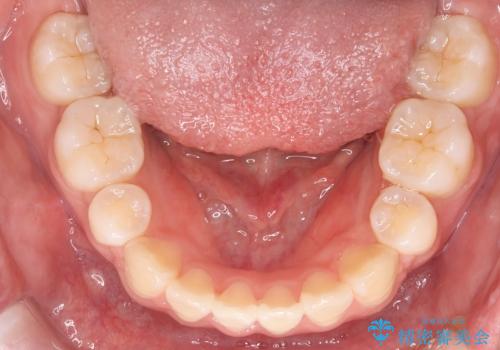

- 前歯のがたつきと口元を気にされて来院されました。

上下4番目の歯を抜歯してがたつきを改善しながら口元を下げる治療計画を立てました。